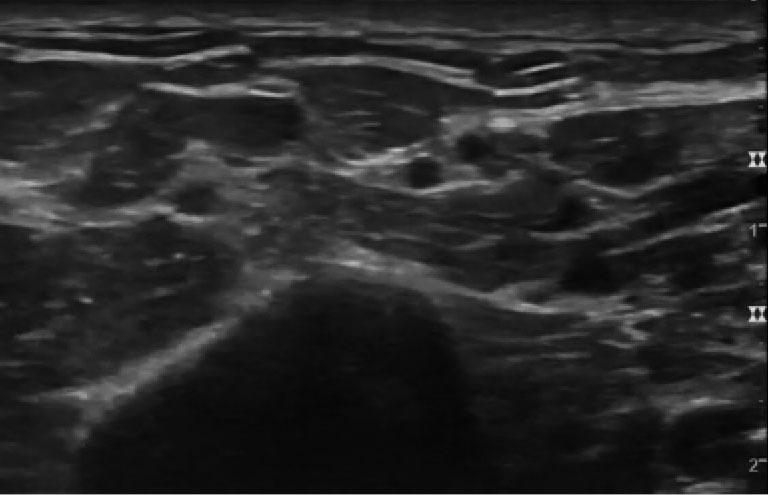

We present a case of 62-year-old Caucasian male with bilateral radicular pain and weakness in the upper extremities after cervical spine surgery for a fracture in a patient that was infected with COVID-19. The patient underwent electrodiagnostic testing, as well as ultrasonographic studies that demonstrated Parsonage Turner syndrome. A literature review on Parsonage Turner syndrome associated with trauma, surgery and COVID-19 was also performed.

我们报告一例62岁的白种男性患者,其在因骨折接受颈椎手术后出现双侧上肢神经根性疼痛和无力,该患者感染了COVID-19。患者接受了电诊断测试以及超声检查,结果显示为Parsonage Turner综合征。我们还对与创伤、手术和COVID-19相关的Parsonage Turner综合征进行了文献综述。